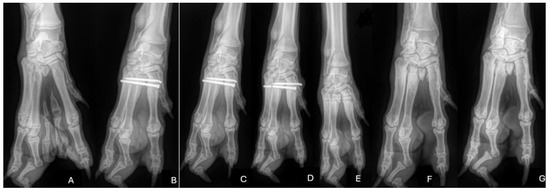

Figure 3.

(A–G): Pre-operative (A) and post-operative (B–G) radiographs of the described case. (A) Pre-operative radiographs showing the metacarpal cleft and bony abnormalities. Note the third digit showing a double conformation with only one claw. (B) Post-operative radiographs—resection of the cleft was performed. A screw and K wire pin was used to stabilise the proximal metacarpals. (C) Follow-up radiographs 6 weeks after surgery showing no change in the position of the implant. (D) Follow-up radiograph 12 weeks after surgery showing a broken screw and migration of the pin. (E) Post-operative radiograph after implant removal. (F) Radiographs 3 months after removal and (G) 14 months after the initial surgery—there is no evidence of subluxation in the proximal region of the metacarpals.

After aseptic preparation, a dorsal approach was made to the third metacarpal (Figure 2B) with the patient in dorsal recumbency. The limb was extended caudally to facilitate the dorsal approach. Starting with a skin incision, the excess digits were isolated with careful blunt and sharp dissection to preserve the vascular structures as much as possible (Figure 2C). After successful isolation, the bony parts were resected (Figure 2D). After complete resection, the carpometacarpal joint space was carefully identified using a 25 G hypodermic needle. Two-point reduction forceps were placed over the proximal metacarpals to reduce the space between the proximal parts of the remaining metacarpals (Figure 2E). A cortical screw (2.0 mm) and a 1.8 mm K wire were then placed across the proximal metacarpals (Figure 3B). The surgical site was irrigated with sterile saline and closed routinely (Figure 2F). Post-operative orthogonal radiographs showed adequate implant positioning and good reduction of the proximal metacarpal row (Figure 3B).

At the six-week follow-up, the patient was presented to our hospital for orthopaedic re-evaluation, including evaluation in stance and ambulation, palpation of the limb, goniometry, and radiographic examination. The dog was in good physical condition. Orthopaedic examination revealed lameness grade I/IV of the right forelimb and no pain was elicited on palpation. The range of motion (ROM) of the operated limb showed an increased angle of extension with a possible carpal extension of 215° and a slightly decreased carpal flexion angle of 42° compared to the described normal ROM of the canine carpal joint (196°/32°) [11]. The sound limb showed an almost normal ROM (195°/30°). Radiographs showed unchanged implant position and incipient fusion of the proximal aspect of the metacarpals (Figure 3C).

At 12 weeks, the dog presented with a sudden onset of severe lameness and was referred to our hospital. Orthopaedic examination revealed grade III/IV lameness and pain on palpation over the proximal metacarpus. Radiographs showed a fracture of the trans-metacarpal screw and migration of the K wire (Figure 3D). Cyclic overload at the transition of the fourth to the fifth metacarpal is most likely the reason for screw breakage with consecutive loosening of the smooth pin after increasing motion between the two metacarpals. Implant removal was discussed with the owners, and the dog received robenacoxib (2 mg/kg, Onsior, Novartis) until revision surgery due to severe discomfort.

After implant removal, post-operative radiographs showed no change in the position of the metacarpals compared to the initial post-operative radiographs (Figure 3E). Four weeks after the removal of the implants, an orthopaedic examination revealed no lameness on ambulation and no pain response upon palpation, but with lameness grade I/IV on extensive exercise reported by the owners. The range of motion (ROM) of the right carpus showed 208° of extension and 39° of flexion.

At the six-month follow-up after the initial surgery, there was no longer any lameness at a walk or trot (Figure 3F). However, the owners still reported grade I/IV lameness after extensive exercise. On palpation, the dog showed no signs of pain, and the carpal joint had an almost normal ROM of 204°/37°. The final radiograph was obtained during spaying 14 months after the initial surgery (Figure 3G), and no lameness was noted by the owners even after extensive exercise. Regarding the abnormal posture of the fourth toe, the dog showed no abnormalities, such as pain upon palpation or splintering at any of the examinations.